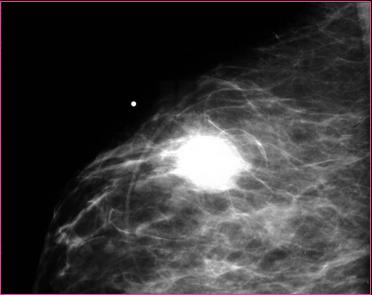

Metallic BB marks palpable lump

Breast mass